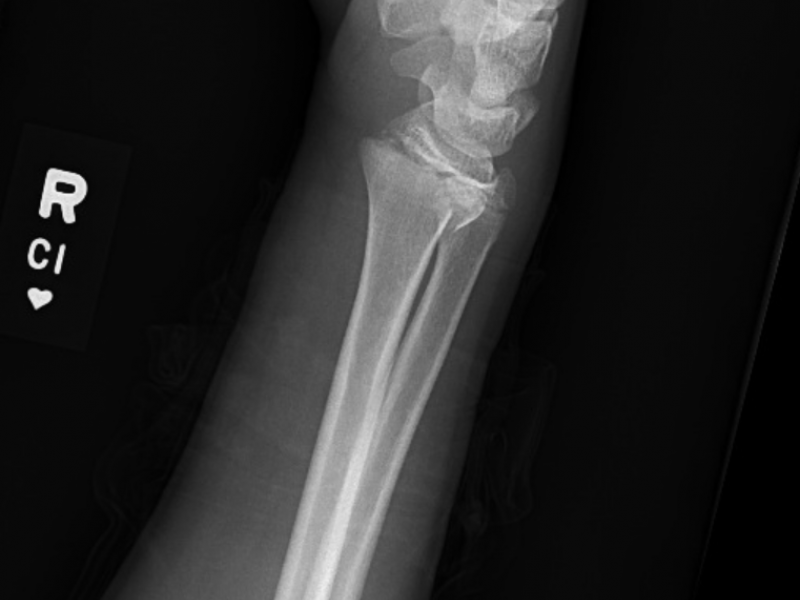

Answer: B. Salter-Harris Fracture Type II In a patient with

Case: A 15 year old girl flipped while snowboarding and